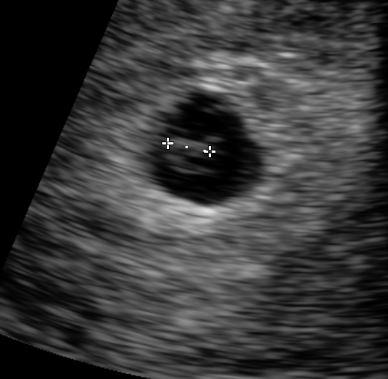

At that point, I had an ultrasound to confirm the pregnancy was not tubal. It wasn’t. I started crying. I cried even harder when I could see the “heart” beating. I was 5.5 weeks along, the baby looked like a tiny, pulsating grain of rice with a balloon around it, and it was the most beautiful thing I’d ever seen.